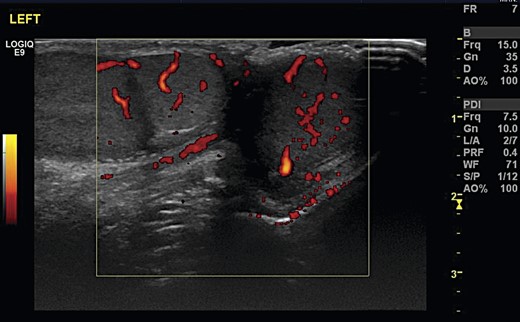

A 12-year-old boy was referred by his GP to the paediatric surgery clinic in a district general hospital with a 6-week history of a lump near the inferior pole of his left testicle. It was non-tender, non-erythematous and had not changed in size or consistency. He was otherwise fit and well, with no family history of urological disorders. On examination, his abdomen was soft and non-tender, with a normal right testis and right spermatic cord. A smooth well-defined lump was palpated on the inferior pole of the left testis. The rest of the testicle had a normal consistency with a normal left cord. Ultrasound demonstrated that both testicles were of a similar size, with normal vascularity and normal epididymi. The palpable lump corresponded to a well-defined 1-cm mass attached to the lower pole of the left testicle (Fig. 1). It had a similar echo pattern to the testicle with normal vascularity (Fig. 2), consistent with the finding of a bilobed testis.

Transverse ultrasonography of the scrotum. A mass is seen attached to the left testicle with the same echo pattern as the normal testicular tissue.